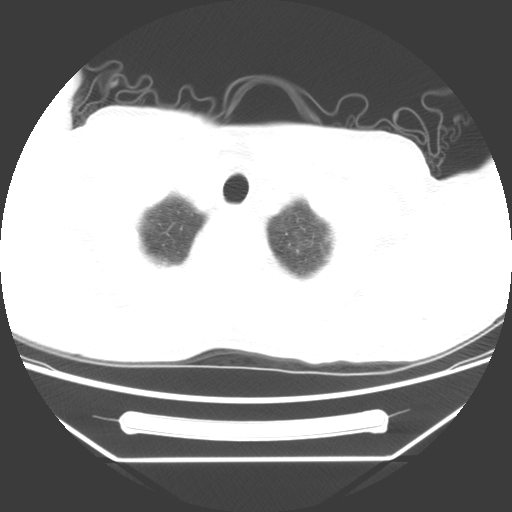

病人55岁,咳嗽,胸闷

忘了传病史了,病人55岁,咳嗽,胸闷

两肺部呈“毛玻璃”状改变,原因待查考虑感染性病变

病人是否发烧,两肺“磨玻璃”影,其间见空气支气管征和碎路石征。考虑肺泡蛋白沉着症。

两肺广泛对称磨玻璃样影,密度不均,考虑机遇性肺部感染。

双肺弥漫磨玻璃样病变,病史很重要。有感冒或发烧史,甲流不除外。无发烧可考虑肺泡蛋白沉积,但肺泡蛋白沉积边缘往往较清晰,与正常肺组织分界清晰

两肺弥漫间质性病变,考虑肺泡蛋白沉着症。建议进一步检查。

两肺“磨玻璃”影,其间见空气支气管征和碎路石征。考虑肺泡蛋白沉着症。

两肺部呈“毛玻璃”状改变,支持肺泡蛋白沉着症。